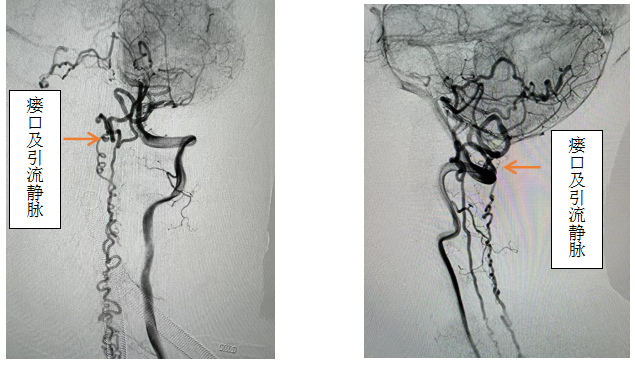

患者女性,56岁,以“双下肢无力伴感觉异常半年,加重2月”主诉入院,入院前先后辗转我省多家医院,效果欠佳。入院时已经行走困难,行颈椎核磁见颈椎蛛网膜下腔异常信号影,请神经外科会诊后考虑硬脊膜动静脉瘘可能性大,转入神外后立即由李帅主治医师行全脊髓血管造影,见“左侧椎动脉V4段发出脑膜支,其远端分支供血形成硬脊膜动静脉瘘,瘘口位于枕骨大孔区,经延髓背侧及腹侧向下引流至胸2椎体节段”。缪星宇主任主持全科病例讨论,讨论考虑患者经脊髓血管造影后诊断明确,手术指征明确,可行硬脊膜动静脉瘘介入栓塞术或开颅阻断术。术中可采取“高压锅”技术防止栓塞胶的返流,降低微导管的到位要求,降低返流空间的要求,使得返流空间安全可控,缩短注胶时间,增加胶的弥散效率,从一定程度上提高栓塞比例,增加患者的安全性。如介入微导管到位困难,可以考虑开颅阻断瘘口,但瘘口位置距离呼吸中枢延髓较近、术中风险大且术后患者恢复时间长。科室讨论后决定利用三级片

先进的复合手术室,首先采用第一方案“高压锅”技术使胶完全封堵瘘口,若不能到位或完全封堵,则采用第二方案,转为开颅阻断瘘口。手术当日,由黄卫东主任医师和李帅主治医师操作,第一根栓塞微导管顺利到达瘘口,第二根微导管接近栓塞微导管后使用弹簧圈顺利形成高压锅塞子,经第一根微导管注入栓塞胶,射线透视下见栓塞胶按预期流向瘘口,栓塞满意后造影示瘘口及引流静脉均未见显影,手术成功。术后患者恢复良好,第二天即下床活动,下肢活动明显恢复,5天后步行出院。